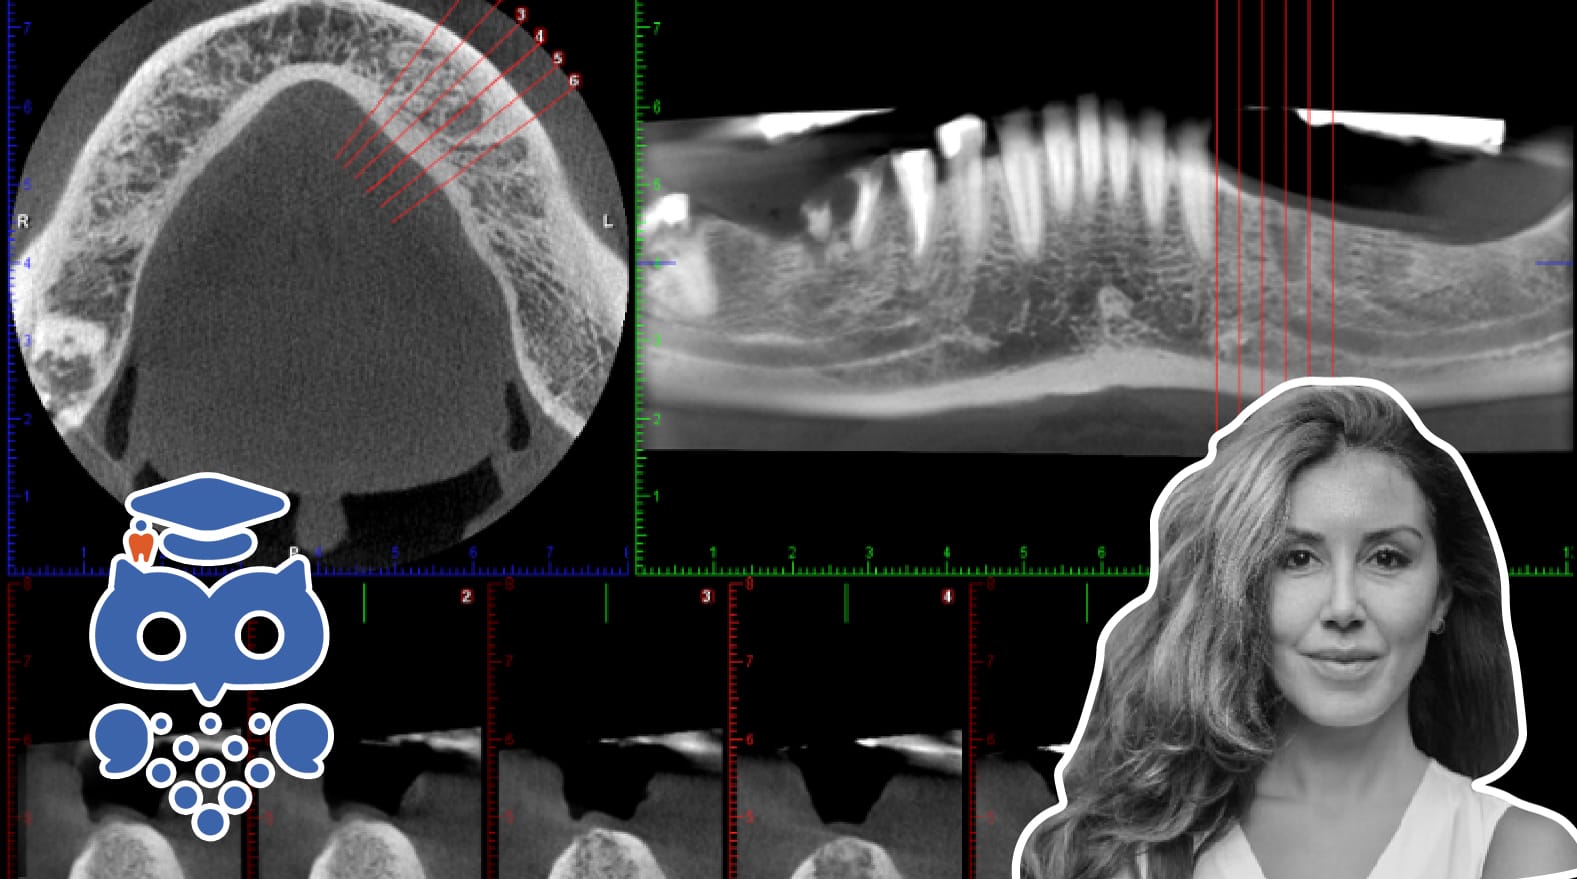

CBCT har sedan 2000-talet fått ökad spridning inom tandvården, särskilt i allmäntandvården. Tekniken ger hög diagnostisk nytta men innebär även högre stråldos, vilket kräver optimering och strikt indikation. Regelverk och specialistkompetens säkerställer säker användning.

Sedan teknikens tillkomst i slutet av 1990-talet och dess introduktion i de nordiska länderna i början av 2000-talet, har den fått en allt större spridning som diagnostiskt verktyg inom såväl den specialiserade sjuk-/tandvården, som hos allmäntandvårdens aktörer. Sannolikt beror den ökade spridningen inom allmäntandvården på ett ökat utbud av flerfunktionella utrustningar där panoramautrustning kompletteras med CBCT (Cone Beam Computed Tomography).

• Prekirurgiska implantatutredningar. Bedömning av tillgänglig benhöjd för implantatinstallation där såväl den bucko-palatinala/-linguala bredden som närheten till anatomiskt viktiga strukturer, såsom mandibularkanalen, kan bedömas.